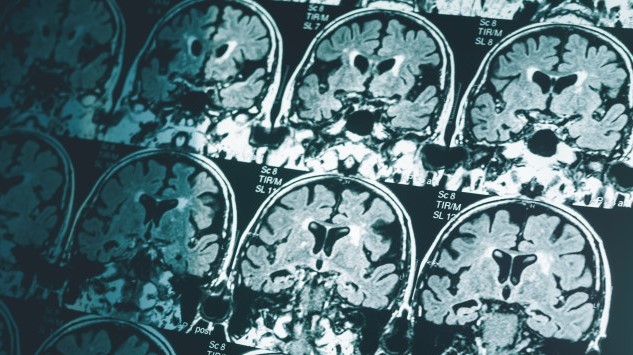

ALZHEIMER'S RESEARCH:

Single brain scan can diagnose Alzheimer’s disease

A single MRI scan of the brain could be enough to diagnose Alzheimer’s disease, according to new research by Imperial College London.

The research uses machine learning technology to look at structural features within the brain, including in regions not previously associated with Alzheimer’s.

The advantage of the technique is its simplicity and the fact that it can identify the disease at an early stage when it can be very difficult to diagnose.

Although there is no cure for Alzheimer’s disease, getting a diagnosis quickly at an early stage helps patients. It allows them to access help and support, get treatment to manage their symptoms and plan for the future.

Being able to accurately identify patients at an early stage of the disease will also help researchers to understand the brain changes that trigger the disease, and support development and trials of new treatments.

The research is funded through the NIHR Imperial Biomedical Research Centre at Imperial College London and by MRC.